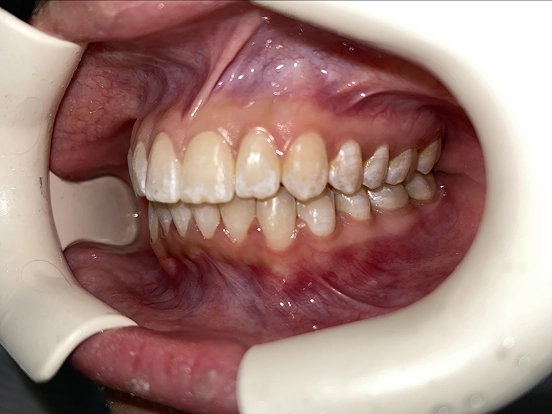

Braces GI

GI achieved a beautifully balanced smile through braces treatment. Over time, the brackets and wires gently moved each tooth into its ideal position, resulting in improved alignment, comfort, and confidence in their everyday smile.